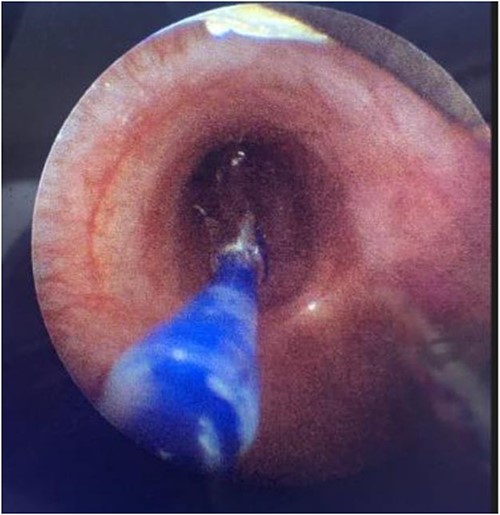

During the procedure in the catheter lab, our team placed a 5 mm balloon over a 3.5 mm bronchoscope, shown in Fig. 1, through the suction port and advanced to the level of the carina. Utilizing fluoroscopy, the balloon was advanced to the narrowed portion of the left main stem bronchus. After this placement was confirmed, the interventional cardiology team tunneled their balloons into the left pulmonary artery and aorta. Markers on the balloons were utilized to ensure the airway and intravascular balloons were adjacent. At this time, both intravascular balloons and the bronchial balloon were simultaneously inflated under direct fluoroscopic visualization, shown in Fig. 2. The bronchial balloon was deflated and removed at this time. The left mainstem bronchus was then visualized, whereas the intravascular dilation and stent placement occurred. During this step of the procedure, the left mainstem bronchus appeared wider compared with its preoperative state and no narrowing of the bronchus was observed upon additional intravascular balloon dilation. The patient improved dramatically within the postoperative period, however needed a further cardiac catheterization to dilate his aortic and pulmonary artery stent. Pediatric otolaryngology was again involved to inflate a balloon to prevent further bronchial compression. Once appropriately prepped, we introduced a 3 mm bronchoscope to the left main bronchus. Under direction of the interventional cardiologist, the balloon introduced into the left mainstem bronchus was visualized under fluoroscopy, advanced to the appropriate position determined by the interventional cardiologist, and then inflated. The balloon size was 6 mm in diameter and 20 mm in length and it was inflated to atmospheric pressure and kept inflated while the interventional cardiologist performed their balloon dilation of left pulmonary artery along with a stent placed in the left pulmonary artery and aorta. The balloon was then deflated and withdrawn and the resultant bronchus was larger in comparison to pre-op. The patient tolerated the operation well.

Fluoroscopic intraoperative images of left mainstem bronchus balloon dilation.